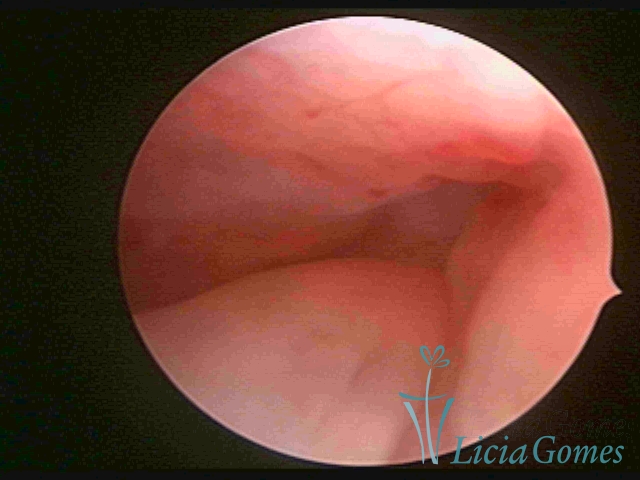

PÓLIPOS ENDOCERVICAIS

São tumores benignos, resultantes da proliferação focal reativa aos processos inflamatórios ou à situações de hiperestrogenismo, e podem ter sésseis (com a base de implantação larga) ou pediculados do epitélio.